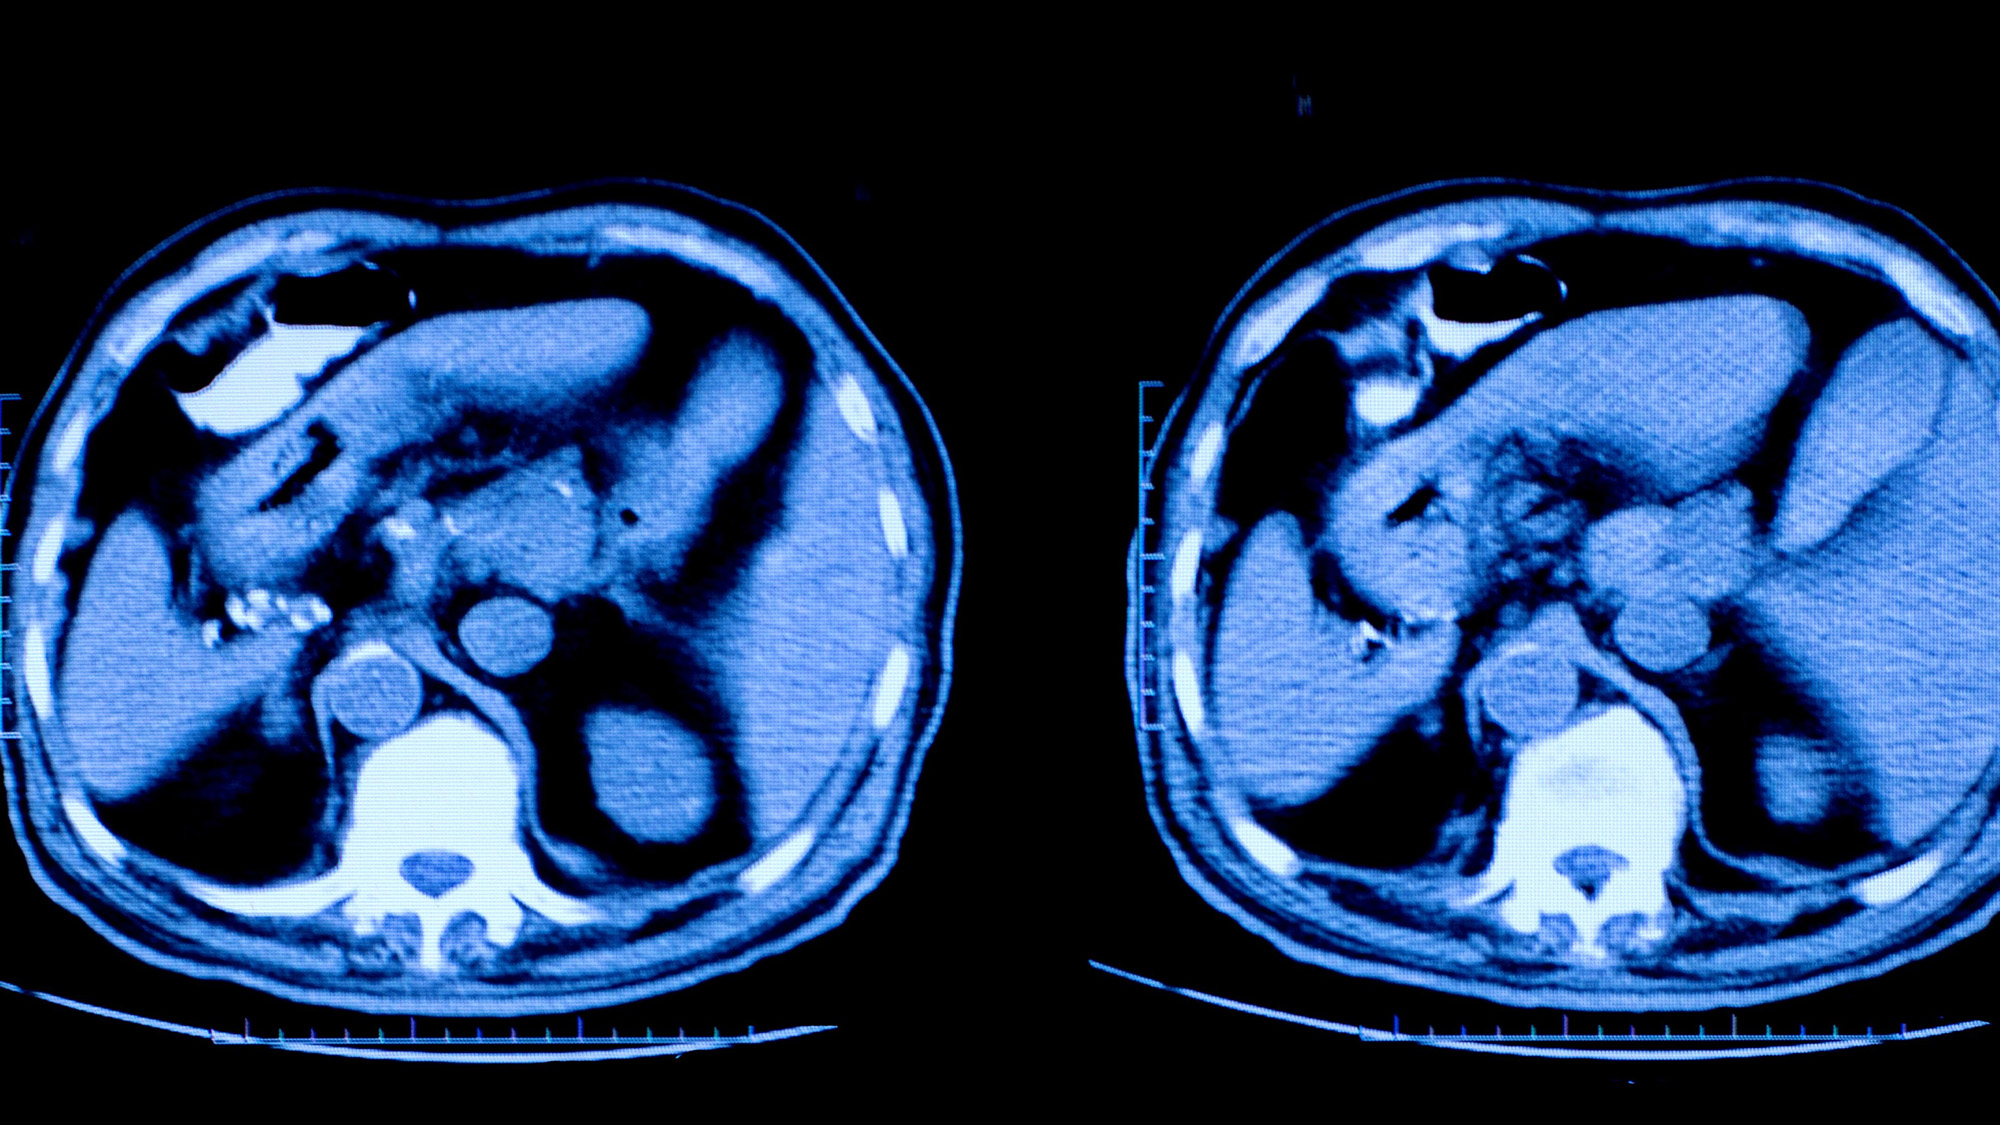

Deep analysis of more than a decade of medical professional liability (MPL) cases reveals that those involving radiologists are most commonly related to missed or delayed diagnoses, in particular, cancer, fractures, and post-procedure complications. While radiologists are most vulnerable to allegations of having misinterpreted a screening or diagnostic image, they are also at risk for failing to adequately communicate their findings to the ordering provider (and, in some cases, patients). Thus, while a primary care provider may have carried out the bulk of a patient’s diagnostic process, missed or delayed diagnosis allegations are often filed against the radiologist.

Compared to physicians in many clinical specialties, radiologists generally have a less established relationship with their patients. They are primarily communicating with peers and the ordering physicians and, typically, are disengaged from the patient’s subsequent course of care. For radiologists, allegations of medical malpractice are almost exclusively focused on issues related to image interpretation, results communication, and follow-up recommendations. The top three contributing factors in cases naming radiologists are:

- Inadequate Patient Assessment: For radiologists, 4 out of 5 cases involve one or more patient assessment issue. These are primarily allegations of misinterpretation—based on subsequent imaging and reads by clinical experts who are retrospectively able to identify anomalies related to the patient’s eventual diagnosis. Radiology cases may also point to a failure to appreciate the relevance of the patient’s results, or to order follow-up imagings.